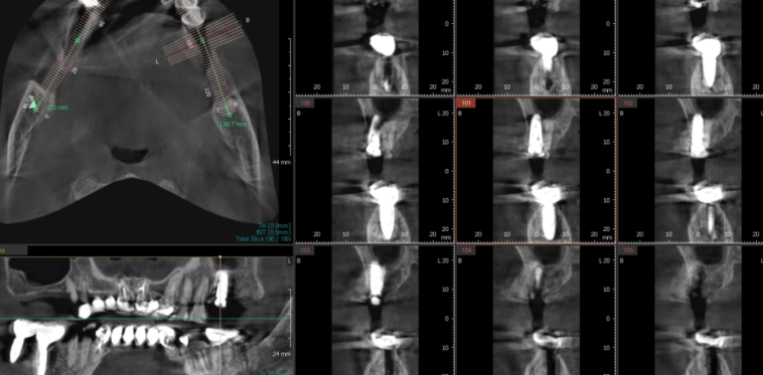

3d-ct

네비게이션 임플란트 방법을 통해 가능한데요.

미리 수술을 예측할 수 있어

불필요한 잇몸 여는 것을 피할 수 있습니다.

3차원적으로 뼈의 형태, 해부학적 구조물

잇몸 모양이 다~~~ 나오는데

굳이 잇몸을 열 필요가 있을까요??